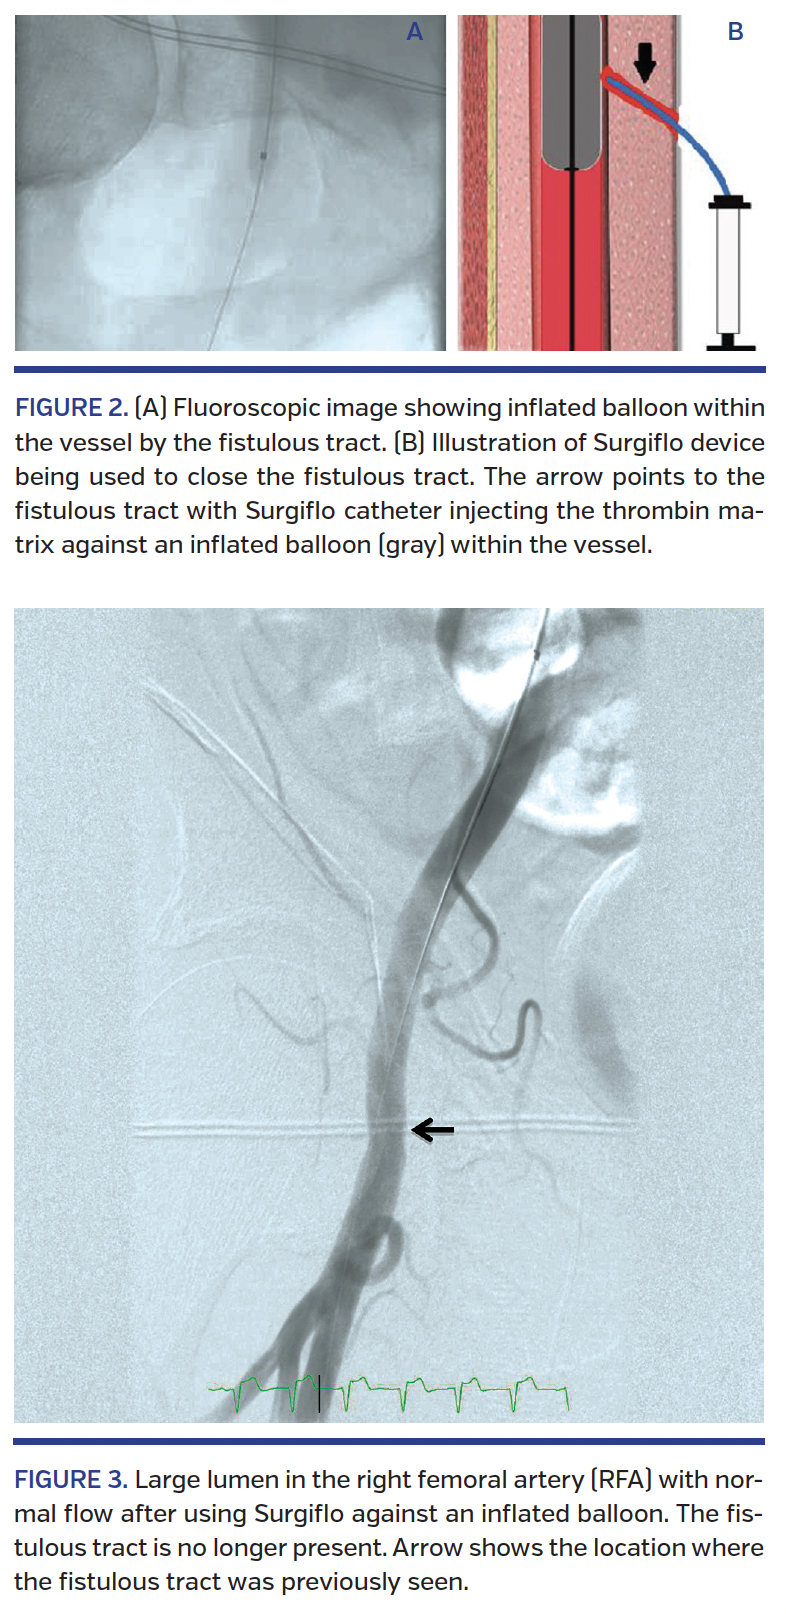

We present the case of a 76-year-old male with past medical history of hypertension, atrial fibrillation, single-vessel coronary artery disease, type-2 diabetes mellitus, and inflammatory arthropathy on hydroxychloroquine and methotrexate. The patient was sent to our institution for TAVR for his severe aortic stenosis. He had complaints of dyspnea on exertion and leg weakness walking up 1 flight of stairs. As part of his TAVR evaluation, the patient underwent computed tomography angiography, which showed a 2.5 cm right common femoral artery pseudoaneurysm likely related to his prior diagnostic catheterization 2 months earlier. Thrombin injection was done at that time with acute thrombosis of the pseudoaneurysm without any complications.4 A subsequent Doppler ultrasound showed thrombosed pseudoaneurysm with no internal flow. One month later, the patient underwent TAVR. Using the modified Seldinger technique and micropuncture kit, a 7 Fr sheath was inserted into the left femoral artery and a 14 Fr e-sheath was placed into the right femoral artery (RFA). Angiographic images of the RFA using crossover technique from the left femoral artery prior to accessing the RFA showed a grossly normal right common femoral lumen without angiographic evidence of aneurysmal dilation or residual pseudoaneurysm or stenosis. A 26 mm Edwards Sapien 3 stent-mounted aortic valve (Edwards Lifesciences) was positioned under fluoroscopic guidance. The valve was confirmed to be in good position with echocardiography. After valve placement, the 14 Fr sheath was removed using the existing sutures. Mild to moderate residual external bleeding was noted from the RFA access site after the Perclose suture closure devices were tied down, with subsequent angiogram from the contralateral 7 Fr access demonstrating extravasation of contrast material from the RFA into a fistulous cutaneous tract and into the adjacent soft tissue (Figure 1). No vessel aneurysm or other areas of contrast extravasation were noticed on the angiographic images. After a period of external manual compression and three subsequent attempts of internal compression with 5-min inflations, a 6 x 4 mm balloon from the contralateral access failed to resolve the bleeding and the decision was made to attempt hemostasis using Surgiflo. The Surgiflo topical sealant was injected into the femoral access tract during inflation of a 6 mm x 4 cm balloon placed at the level of persistent bleeding at the RFA access site. A multibend flex-tip catheter, provided with the hemostatic matrix kit, was used to inject Surgiflo hemostatic matrix within the access tract between the inflated balloon and the site of extravasation (Figure 2). The Surgiflo was allowed to dwell for 5 minutes with the balloon inflated, after which the balloon was deflated. Angiographic images showed no residual contrast extravasation and there was a large lumen at the puncture site with normal blood flow to the distal vessel (Figure 3). The patient tolerated the procedure well, with an estimated blood loss of <200 mL. The patient was monitored in the intensive care unit for 1 night and his length of stay in the hospital was 4 days. His only postprocedural complication was a new left bundle-branch block, which ultimately was treated with permanent pacemaker insertion.

Three contraindications are listed from manufacturers when using Surgiflo. The first is that it cannot be used in the closure of skin incisions because it may interfere with the healing of skin edges. The second is that it cannot be used in patients with known allergies to porcine gelatin. The third is that it should not be used within intravascular compartments because of the risk of embolization. In our case, the Surgiflo gel matrix was used under direct fluoroscopic guidance against an inflated crossover balloon to achieve closure of the fistulous tract from the RFA access site.9 We believe the presence of an intraluminal balloon is critical to prevent inadvertent intraarterial injection of the Surgiflo gel matrix. The use of an intraarterial balloon and an extravascular sealant also comprises the foundation for the MynxGrip vascular closure device (Cordis Corporation); however, the MynxGrip deploys a small balloon directly through the arteriotomy access site and injects a polyethylene glycol sealant (a water-soluble, bioinert, non-thrombogenic polymer) extravascularly through a small sheath.10 Unlike the use of a crossover balloon and Surgiflo as described in this manuscript, the MynxGrip is not suitable for use with large-caliber access sheaths and requires retained wire access. Overall, in this case, good arterial flow was demonstrated distally at the end of the procedure. Our patient did not have any complications at the time of the 2-month follow-up visit.